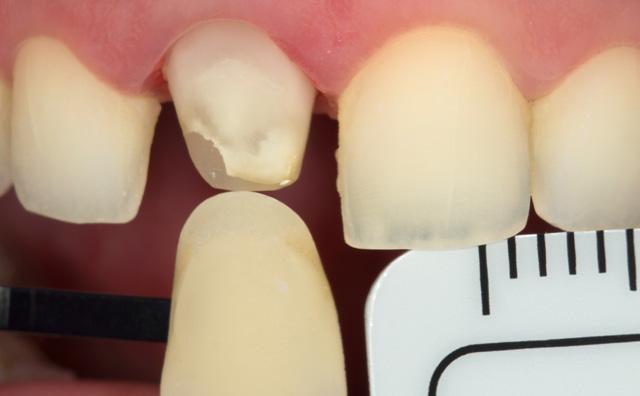

The patient, a young male, was unhappy with the appearance of his maxillary anterior teeth. Several years ago, his central incisors had been restored with composite. These existing restorations had defective and heavily discoloured margins, while their shade did not match the adjacent natural tooth structure. The maxillary lateral incisors were peg-shaped (microdontia). Economic considerations and the desire to save as much natural tooth structure as possible made the team decide to restore all four maxillary incisors with composite. CLEARFIL MAJESTY™ ES-2 Premium became the material of choice as it eliminates the need for complicated shade combination formulas and supports predictable outcomes.

We decided to restore the central incisors first and then focus on the lateral incisors. The tooth shade was determined using the VITA™ classical A1-D4 shade guide, while composite buttons were applied to the teeth to verify the determined shade combination. In order to simplify the restoration procedure, a palatal silicon index was produced before removing the existing restorations.

Fig. 2 Intraoral image of the initial situation with defective composite restorations and microdonts. Two composite buttons on the right lateral incisor are used to verify the determined shade combination.

Fig. 3 Central incisors after removal of the old restorations and the beveling of the enamel.

During minimally invasive tooth preparation, bevels were created at the margins to provide for a smooth optical transition from the natural tooth structure to the composite.

An adhesive (CLEARFIL™ Universal Bond Quick) was applied after selective etching of the enamel to achieve a strong bond. With the aid of the silicon index, it was easy to create the palatal shells of the restorations with CLEARFIL MAJESTY™ ES-2 Premium in the shade A3E (enamel), which matches the determined tooth shade A3. The dentin core was built up with the same composite in the recommended shade A3D (dentin), mamelons were modelled and some CLEARFIL MAJESTY™ ES-2 Premium in the shade WD added for the incisal halo, while some individual effects (like enamel cracks) were imitated with brown stain. The build-up was finalized in the interproximal and labial areas with composite in the shade A3E. Between the central incisors, a wedge was used to retract the papilla and facilitate the designing of the interproximal contact area. The finished and pre-polished restorations already had a natural appearance.